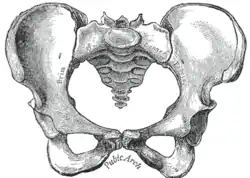

![]() |

| Comparação entre uma pelve androide (esquerda) e uma ginecoide (direita). | |

Os serviços obstétricos tradicionais dependiam fortemente da pelvimetria na condução do parto para decidir se o parto vaginal natural ou operatório era possível, ou se e quando recorrer a uma cesariana.[9] Mulheres cujas pelves eram consideradas pequenas recebiam cesarianas em vez de parirem naturalmente.

A obstetrícia tradicional caracterizou quatro tipos de pelves:

- Ginecoide: forma ideal, com abertura superior arredondada a levemente oval (entrada obstétrica ligeiramente menos transversa).

- Androide: abertura triangular, espinhas isquiáticas proeminentes, arco púbico mais angulado.

- Antropoide: o maior diâmetro transverso é menor que o diâmetro obstétrico ântero-posterior.

- Platilipeloide: abertura superior achatada, com diâmetro obstétrico reduzido.